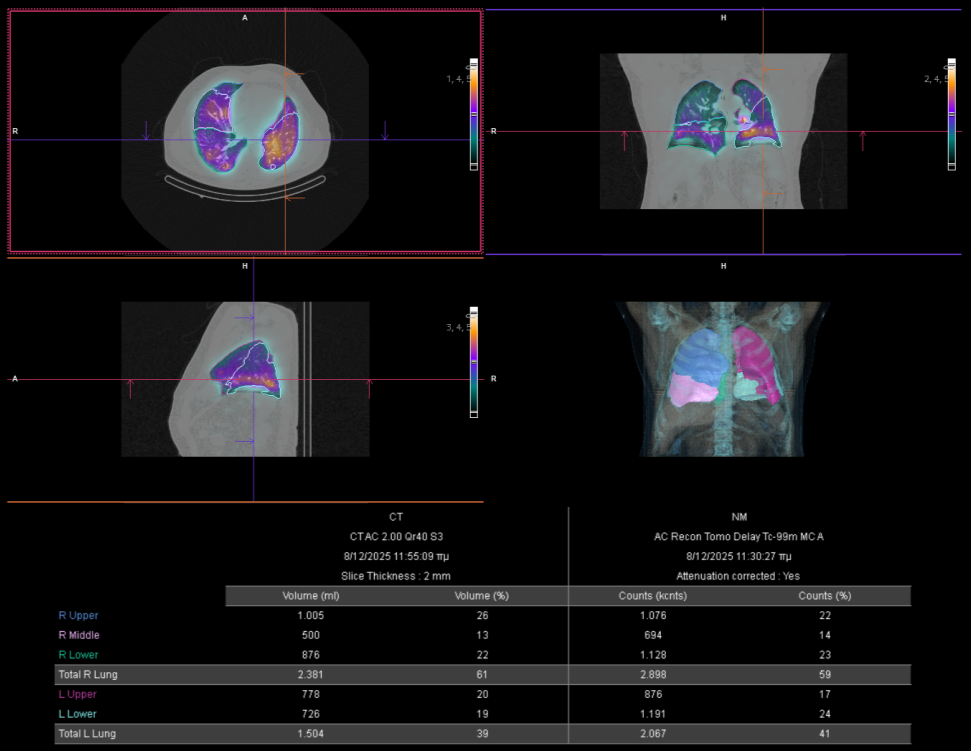

Με τη SPECT‑CT ποσοτικοποίηση υπολογίζουμε απορροφούμενες δόσεις σε όγκους και όργανα‑στόχους (νεφροί, σιελογόνοι, ήπαρ, μυελός κ.ά.). Αυτό:

Η θεραπεία με Ύτριο-90 SIR-Spheres (Y-90) αποτελεί μια εξειδικευμένη τεχνική εκλεκτικού ενδοαρτηριακού εμβολισμού, η οποία στοχεύει αποκλειστικά τον όγκο μέσω των ηπατικών αγγείων, επιτρέποντας την εναπόθεση σωματιδίων που εκπέμπουν ραδιενέργεια τοπικά με ελάχιστη ακτινική επιβάρυνση στους υγιείς ιστούς. Η διαδικασία περιλαμβάνει λεπτομερή προθεραπευτικό αγγειογραφικό σχεδιασμό με αξιολόγηση της αγγειακής ανατομίας και χορήγηση ενός ιχνηθέτη για την ανίχνευση τυχόν διαφυγής (πχ. lung shunt), εξασφαλίζοντας μέγιστη ασφάλεια και εξατομίκευση. Η επιλογή της δόσης γίνεται πλέον με σύγχρονα υπολογιστικά μοντέλα δοσιμετρίας και εξειδικευμένα λογισμικά (όπως MIM ή SIR-TeX platform), τα οποία επιτρέπουν ακριβή αποτύπωση του όγκου της νόσου στο ήπαρ, υπολογισμό του πραγματικού tumor burden και εκτίμηση της απορροφούμενης δόσης τόσο στον όγκο όσο και στο υγιές ηπατικό παρέγχυμα. Μετά τη θεραπεία, πραγματοποιείται έλεγχος κατανομής της ακτινοβολίας (μέσω Bremsstrahlung SPECT/CT ή PET/CT), ενώ ακολουθεί στενή απεικονιστική και κλινική παρακολούθηση για την αξιολόγηση της ανταπόκρισης, την εκτίμηση τυχόν τοξικοτήτων και τον σχεδιασμό επόμενων βημάτων στην ογκολογική στρατηγική του ασθενούς. Πρόκειται για μια ιδιαίτερα αποτελεσματική θεραπευτική επιλογή σε πρωτοπαθείς ηπατικούς όγκους και σε ηπατικές μεταστάσεις, ειδικά όταν οι συμβατικές θεραπείες έχουν περιορισμένη αποτελεσματικότητα ή δεν είναι πλέον εφικτές.

Η θεραπεία με Lu-177 DOTATATE (PRRT – Peptide Receptor Radionuclide Therapy) αποτελεί μια από τις πλέον εξελιγμένες μορφές στοχευμένης ραδιονουκλιδικής θεραπείας για νευροενδοκρινείς όγκους του γαστρεντερικού και του παγκρέατος, αξιοποιώντας την υπερέκφραση των υποδοχέων σωματοστατίνης στους νεοπλασματικούς ιστούς. Η διαδικασία περιλαμβάνει τον ακριβή προσδιορισμό της έκτασης της νόσου μέσω Ga68 DOTATATE PET/CT, την επιβεβαίωση υψηλής έκφρασης υποδοχέων SSTR και στη συνέχεια τη χορήγηση του Λουτέσιο-177 DOTATATE, το οποίο δεσμεύεται εκλεκτικά στους ανωτέρω υποδοχείς. Η ενέργεια του β-εκπομπού Λουτέσιου επιτρέπει στοχευμένη κυτταροτοξική δράση μέσα στον όγκο, με ελάχιστη διασπορά σε υγιείς ιστούς. Η σύγχρονη πρακτική ενσωματώνει ειδικά λογισμικά δοσιμετρίας, που υπολογίζουν την απορροφούμενη δόση σε κρίσιμα όργανα (ήπαρ, νεφροί, μυελός) και την πραγματική δόση στον όγκο, επιτρέποντας εξατομικευμένο σχεδιασμό και βελτιστοποιημένη θεραπευτική στρατηγική. Μετά από κάθε κύκλο θεραπείας πραγματοποιείται απεικονιστικός έλεγχος, αξιολόγηση τοξικοτήτων και συνολική εκτίμηση ανταπόκρισης, καθοδηγώντας τις επόμενες φάσεις της θεραπείας. Το Lu-177 DOTATATE έχει αποδειχθεί εξαιρετικά αποτελεσματικό στη σταθεροποίηση και συχνά στη συρρίκνωση της νόσου, παρατείνοντας την επιβίωση και βελτιώνοντας σημαντικά την ποιότητα ζωής των ασθενών.